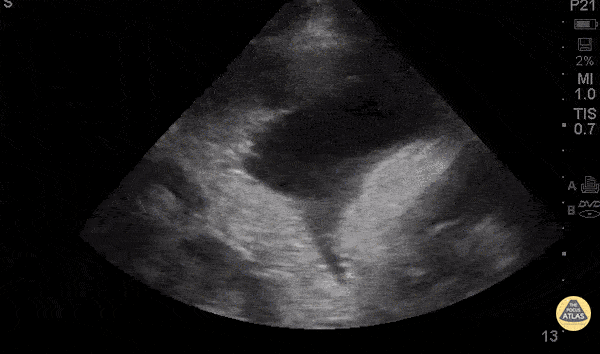

Pulmonary - Malignant Effusion

71 y/o F w/ hx of COPD/asthma, lung cancer on chemotherapy with recent admission for malignant pleural effusion (chest tube placed), presenting with for worsening cough/wheezing/shortness of breath for 1 day. No fevers or chest pain. The clip shows a large fluid collection in the left anterior chest with loculations and mediastinal shift to the right. Cardiothoracic surgery drained 2.7L of hemorrhagic pleural effusion. Dr. Vicky Lam - Kings County Emergency Medicine